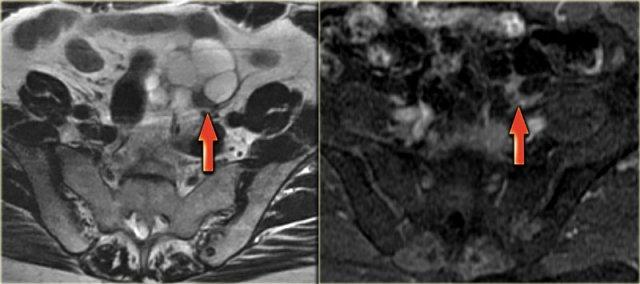

Nang hoàng thể trên MRI: hình ảnh chuỗi xung T2W mặt cắt ngang cho thấy nang hoàng thể đang thoái triển (mũi tên).

Đây là hình ảnh bình thường.

Buồng trứng phải cũng bình thường.

Hình ảnh chuỗi xung T2W mặt cắt ngang và mặt cắt đứng dọc của cùng một bệnh nhân.

Buồng trứng phải chứa nhiều nang đơn giản tăng tín hiệu T2 với bờ mỏng và không có thành phần đặc.

Trên hình mặt cắt ngang, có một tổn thương giảm tín hiệu T2, tức là nang phức tạp (mũi tên).

Có một lượng nhỏ dịch cổ trướng quanh buồng trứng phải, nhưng không đủ để gợi ý lo ngại về khả năng u tân sinh.